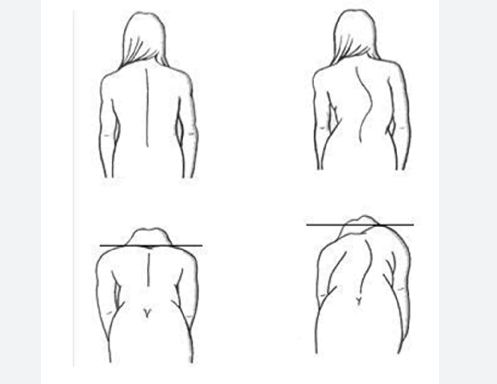

Einer der offensichtlichsten Anhaltspunkte für die Beurteilung der Skoliose ist das Vorhandensein sichtbarer Anzeichen einer Wirbelsäulendeformität. Diese Anzeichen können sein:

a. Ungleiche Schulterhöhe: Ein deutlicher Unterschied in der Schulterhöhe kann ein frühes Anzeichen für eine Wirbelsäulenverkrümmung sein.

b. Asymmetrie in den Hüften oder der Taille: Ungleiche Hüften oder eine ausgeprägte Taille auf einer Seite können auf ein mögliches Wirbelsäulenproblem hinweisen.

c. Rippenbuckel: Ein sichtbarer Rippenbuckel, insbesondere beim Vorwärtsbeugen, kann auf eine Skoliose hinweisen.

Eltern, Lehrer und die Betroffenen selbst sollten auf diese visuellen Anzeichen achten, da sie oft die ersten Hinweise auf mögliche Unregelmäßigkeiten der Wirbelsäule sind.

8. Bei körperlichen Routineuntersuchungen festgestellte Asymmetrie:

Bei Routineuntersuchungen durch medizinisches Fachpersonal, einschließlich Kinderärzten und Orthopäden, können Asymmetrien festgestellt werden, die auf die Notwendigkeit einer Skolioseuntersuchung hindeuten. Bei Routineuntersuchungen beurteilen die Gesundheitsdienstleister die Ausrichtung von Schulter und Hüfte, um Anzeichen von Asymmetrie zu erkennen. Alle beobachteten Unregelmäßigkeiten können eine Überweisung zur Untersuchung der Skoliose erforderlich machen.